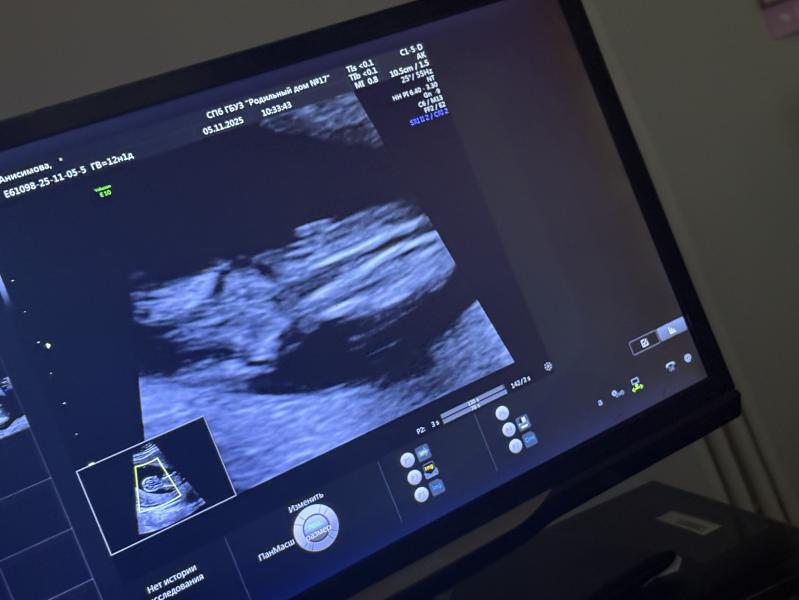

Ну что как думаете можно выдыхать и верить крови и узи?🫣😅хотя мне кажется я не поверю пока не рожу😂 на втором фото увеличено)

Девочка 100%😍 Я тоже такую картинку увидела на узи,уже и не надеялась на пирожок😊 долго не могла поверить в то,что точно девочка,поверила окончательно когда достали и показали прелести ☺️☺️☺️